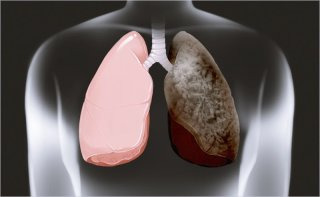

폐 섬유증이란 폐 조직이 점차 딱딱하게 변하면서 정상적인 호흡 기능을 잃어가는 질환이다. 우리 폐는 수많은 폐포로 구성돼 있으며, 이 폐포에서 산소와 이산화탄소 교환이 이뤄진다. 그러나 섬유화가 진행되면 유연해야 할 폐포 벽이 흉터 조직으로 대체되며 탄성을 잃는다.

마치 말랑하던 스펀지가 굳은 가죽처럼 변하는 과정이다. 이로 인해 숨을 들이마셔도 공기가 충분히 들어가지 않고, 내쉴 때도 잔여 공기가 남아 답답함을 유발한다. 문제는 이러한 변화가 매우 서서히 진행된다는 점이다.